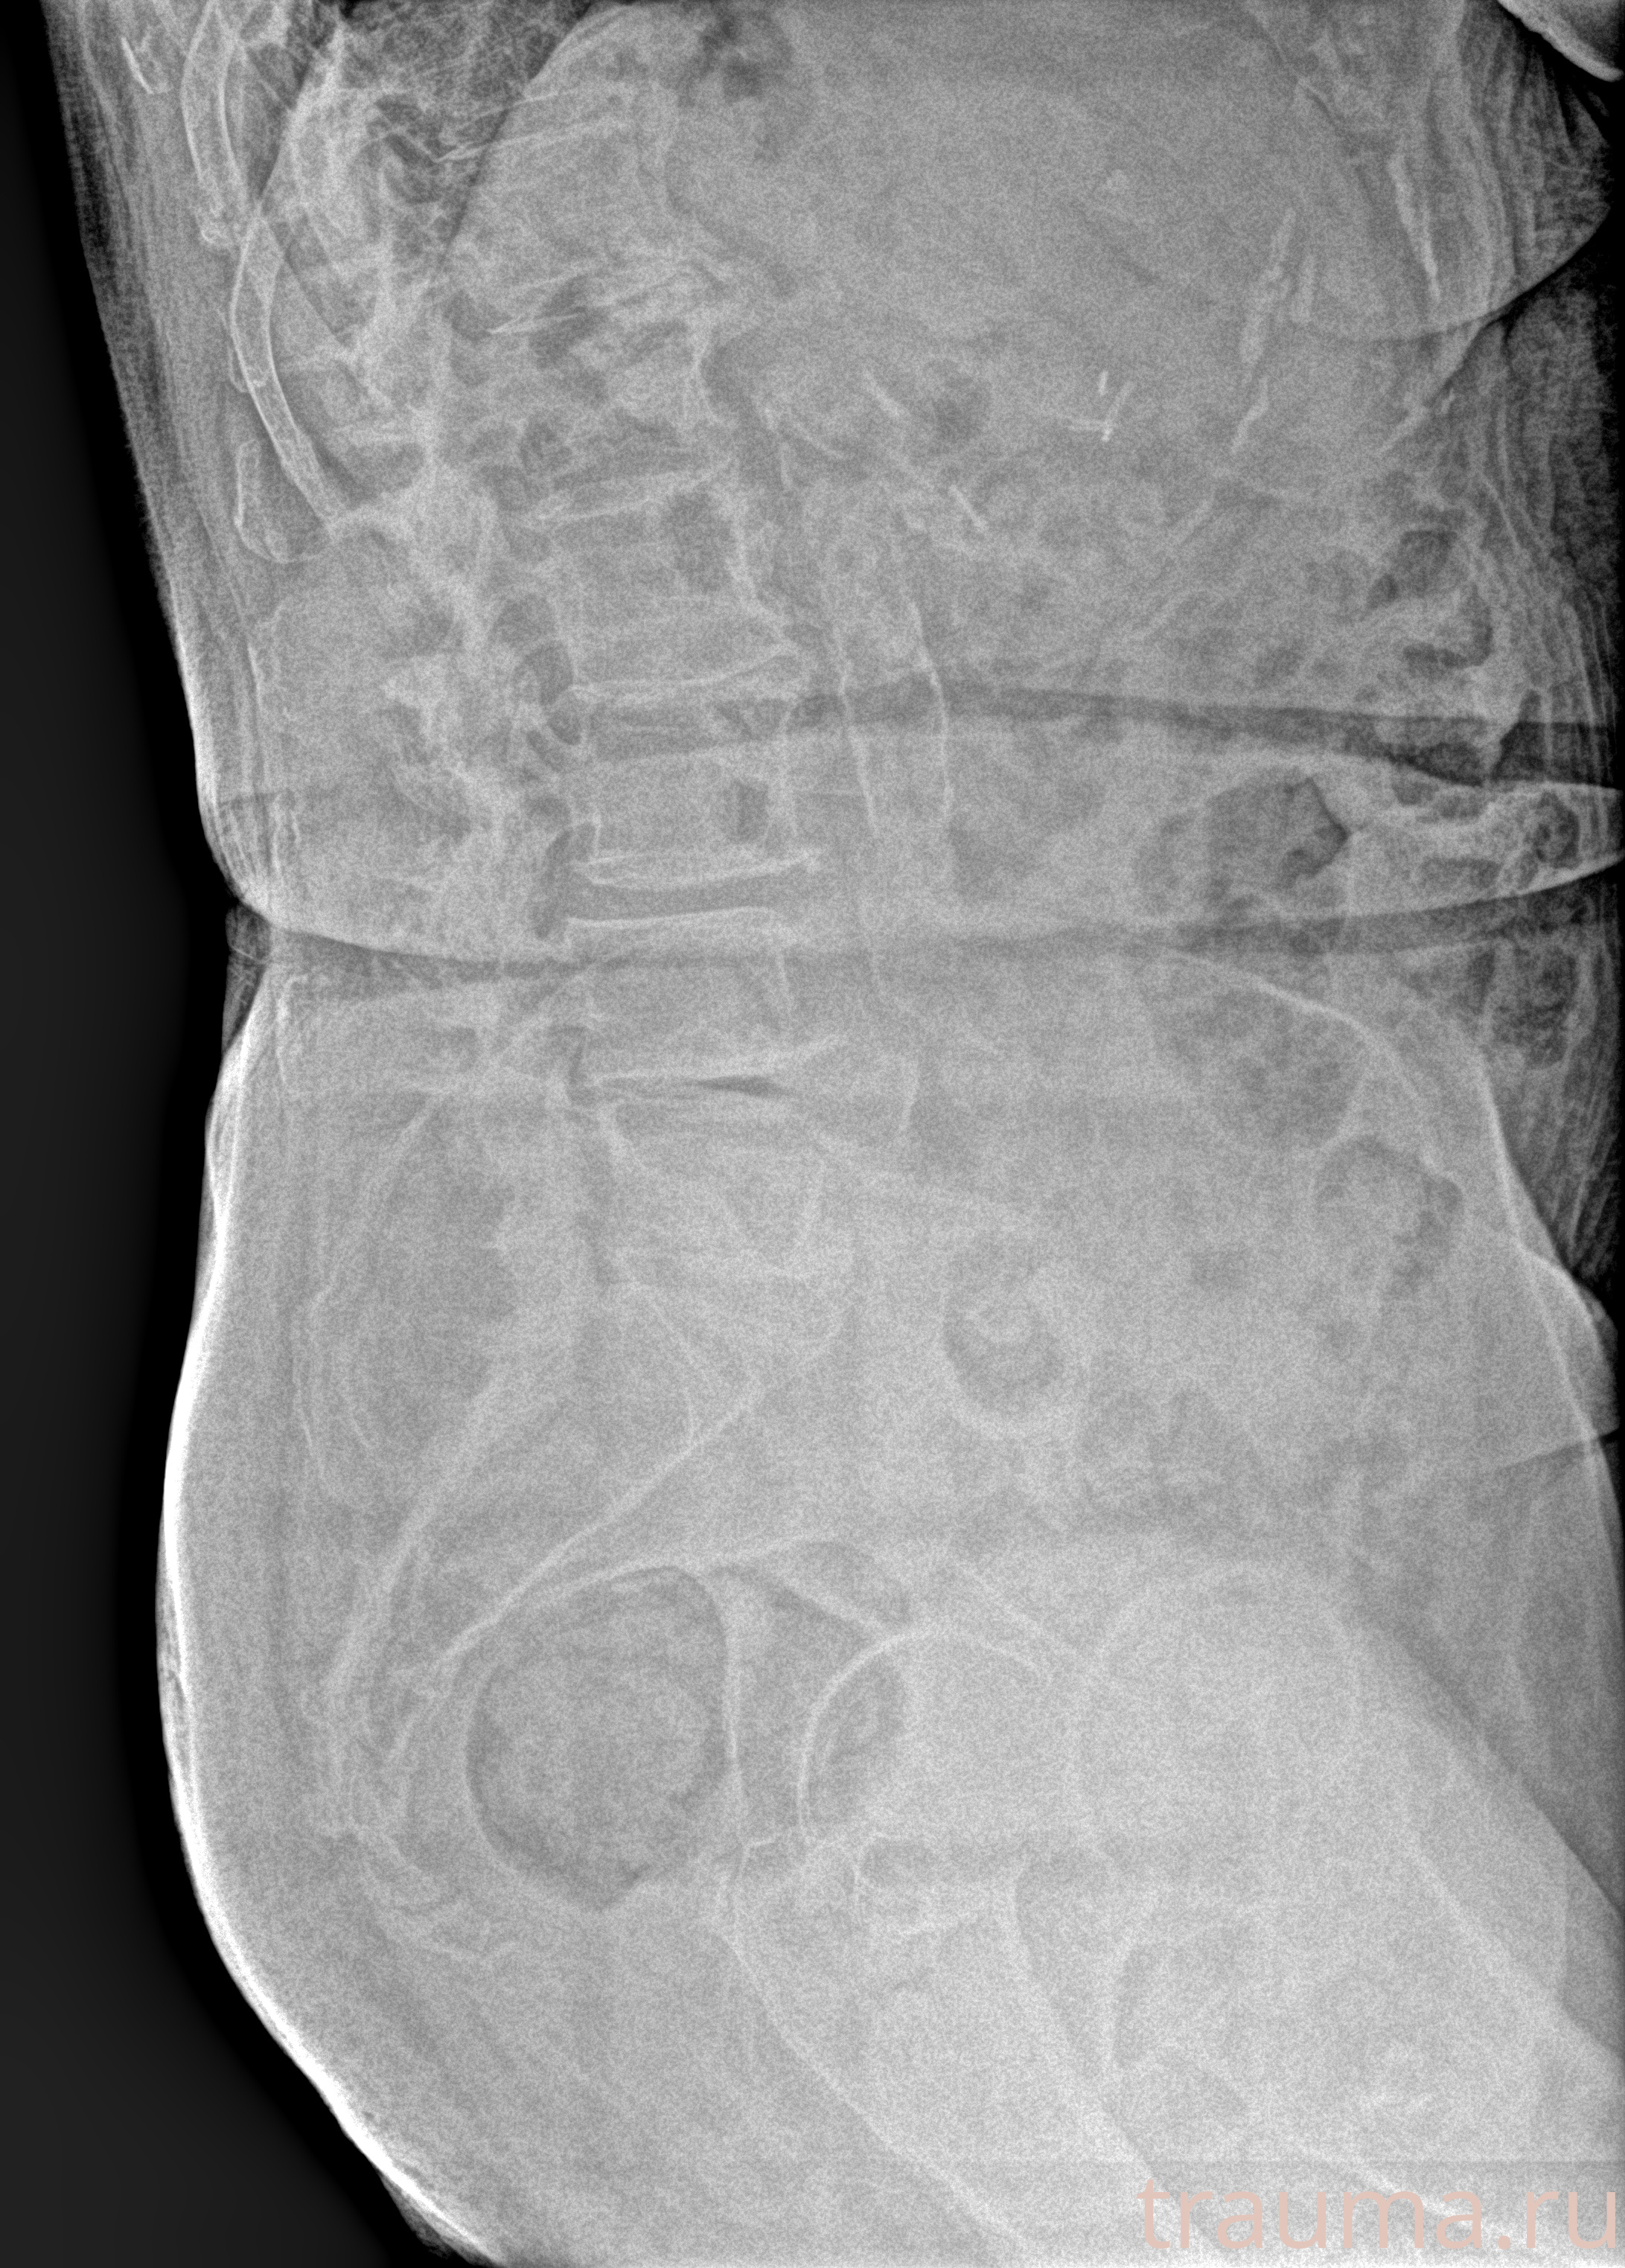

Рентген на дому: по вашему адресу приезжает врач-рентгенолог, травматолог-ортопед с мобильным рентгеновским аппаратом, проводит диагностику травмы или заболевания, делает необходимые рентгенограммы, дает рекомендации по дальнейшему лечению. Получить качественные снимки в домашних условиях возможно благодаря уникальной методике, разработанной МосРентген Центром для института  Склифосовского